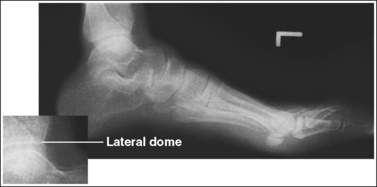

See Figures 6-23 and 6-24 and Box 6-7.

The foot is in a lateral projection. The talar domes are superimposed, the tibiotalar joint is open, and the distal fibula is superimposed by the posterior half of the distal tibia.

• To obtain a lateral foot projection, begin with the patient in a supine position with the leg extended and the foot dorsiflexed until its long axis forms a 90-degree angle with the lower leg (Figure 6-26). Rotate the patient toward the affected leg until the lateral foot surface is against the IR, and then adjust the degree of rotation until this surface is aligned parallel with the IR (Figure 6-27). For most patients, this positioning places the lower leg parallel with the imaging table. If this is not the case, as for a patient with a large upper thigh, the foot and IR should be elevated with an immobilization device until the lower leg is brought parallel with the imaging table.

• Accurate longitudinal arch visualization: This position may not bring the medial plantar foot surface perpendicular to the IR. If this is so, do not try to adjust the leg in an attempt to position this surface perpendicular to the IR. The true relationship of this surface to the IR and the metatarsals to one another depends on the height of the patient's longitudinal arch and the incline of the calcaneus. Adjusting the patient's plantar surface may result in poor talar dome positioning and an erroneous longitudinal arch height.

The height of the longitudinal arch can be determined by measuring the amount of cuboid demonstrated posterior to the navicular bone. The average lateral foot projection demonstrates approximately 0.5 inch (1.25 cm) of the cuboid, as shown in Figure 6-23. Because the bones that form the foot arch are held in position by ligaments and tendons, weakening of these tissues may result in a decreased or low arch. On a lateral foot projection, this decrease in arch height is demonstrated as a decrease in the amount of cuboid demonstrated posterior to the navicular bone. Figure 6-20 shows a lateral foot projection of a patient with a low longitudinal arch and approximately 0.25 inch (0.6 cm) of cuboid posterior to the navicular bone, whereas Figure 6-22 shows a patient with a high arch and approximately 0.75 inch (2 cm) of cuboid posterior to the navicular bone.

• Talar domes. The domes of the talus are formed by the most medial and lateral aspects of the talar's trochlear surface. On a lateral foot projection, they appear as domed structures that articulate with the tibia. On a properly positioned lateral foot projection, the talar domes should be superimposed and appear as one and the tibiotalar joint should be open. When the lateral foot is mispositioned, the domes are individually demonstrated, and they obscure the tibiotalar joint. Proximal-distal misalignment of the domes results from poor knee and lower leg positioning, and AP misalignment of the domes results from poor foot positioning.